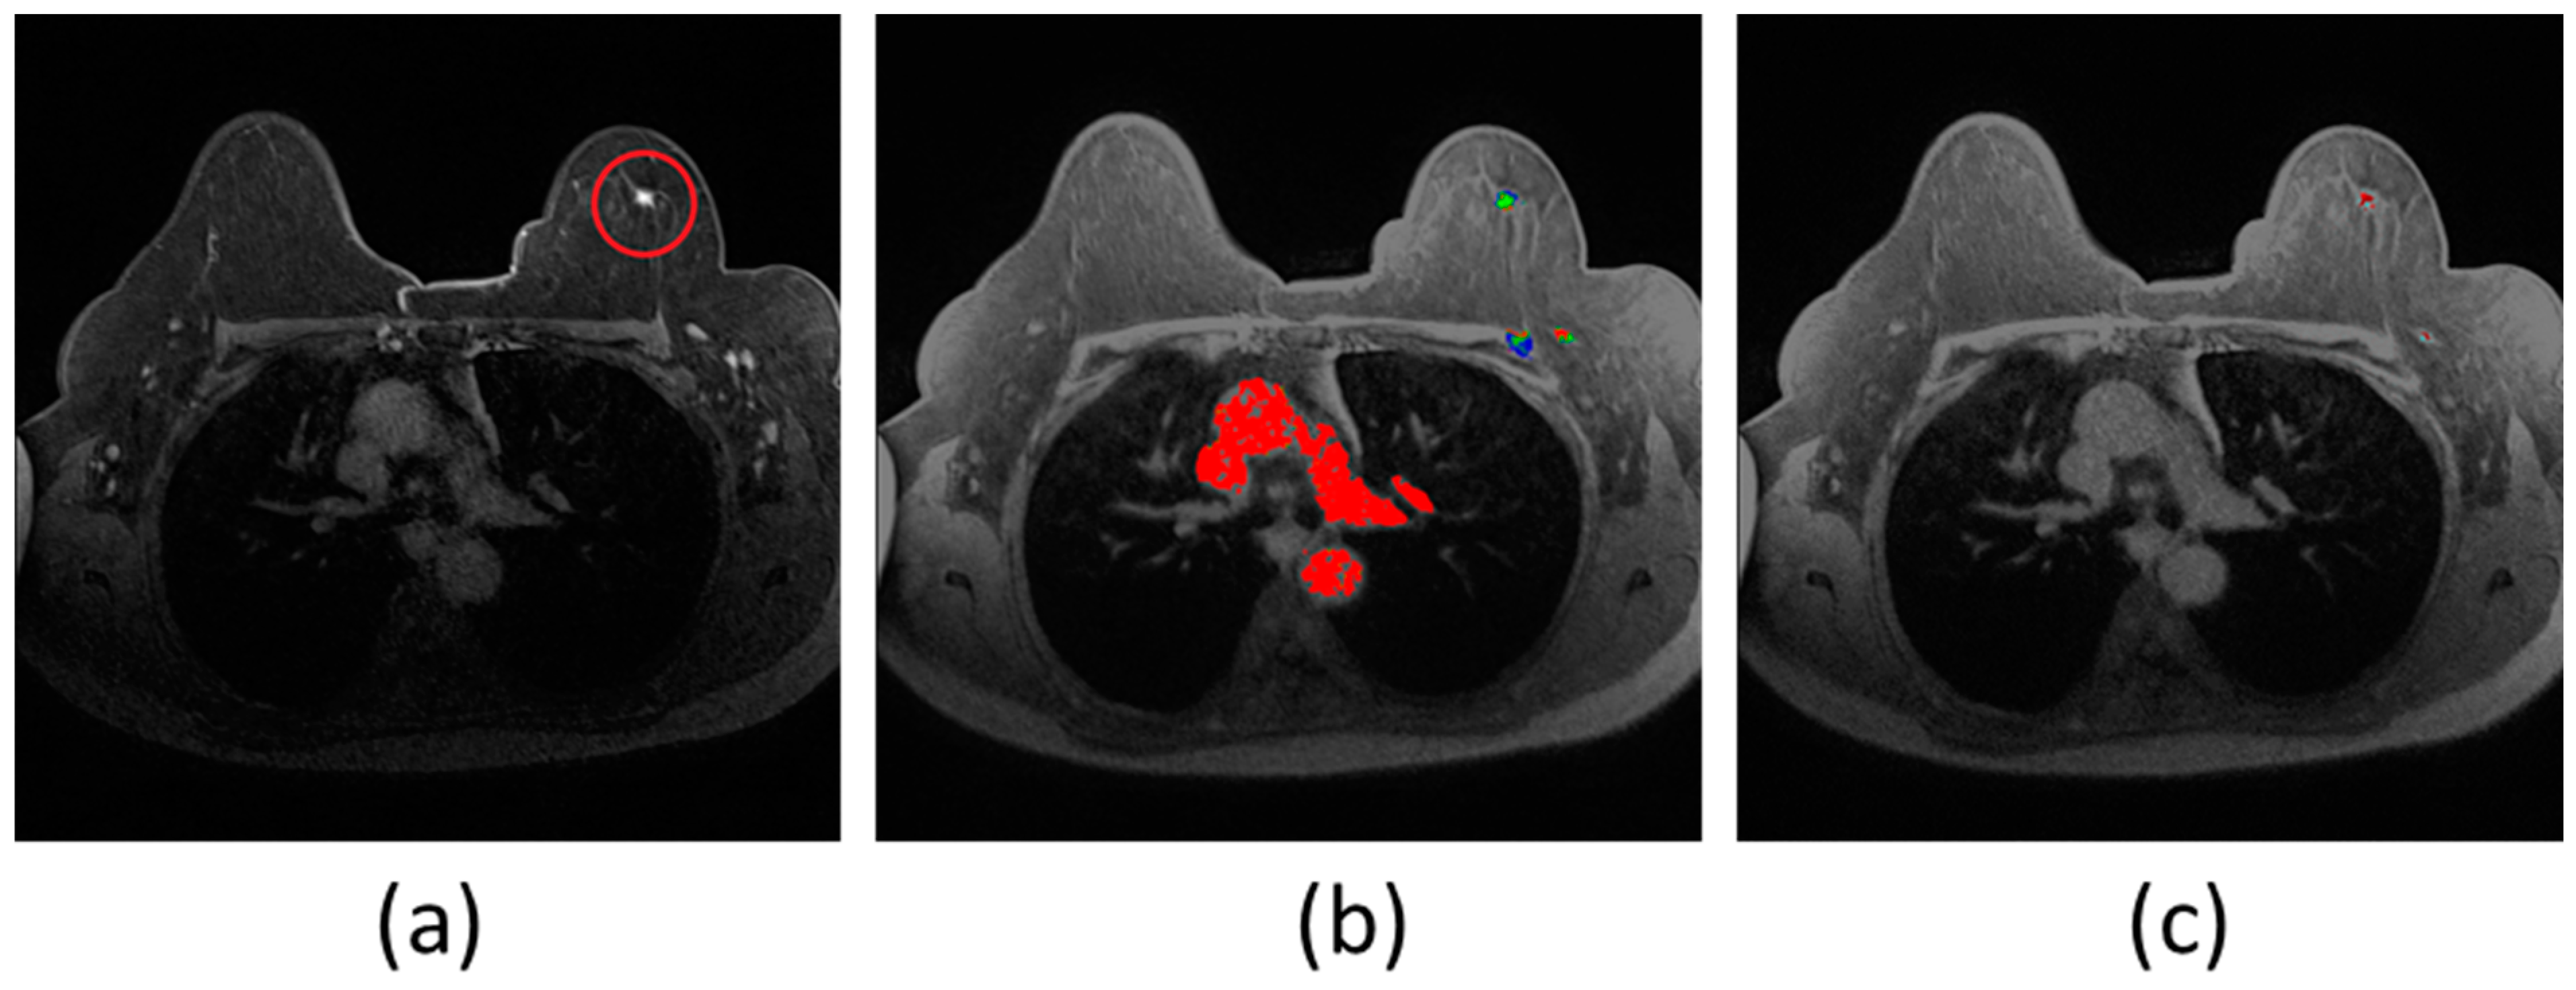

6. Image Segmentation¶

Task: Classify every pixel in an image - the most detailed form of visual understanding

Medical Applications:

- Organ segmentation for surgical planning and volume measurement

- Tumor delineation for treatment planning and monitoring

- Cell segmentation in microscopy images

- Tissue type differentiation (gray/white matter, CSF)

Types:

- Semantic Segmentation: Labels all pixels of the same class identically

- Instance Segmentation: Distinguishes between different instances of the same class

U-Net Architecture:

- Designed specifically for biomedical image segmentation

- Excellent performance with limited training data

- Key features:

- Encoder-decoder structure (U-shaped)

- Skip connections between corresponding encoder-decoder levels

tl;dr - For medical image segmentation, U-Net uses a U-shaped CNN. The encoder (left) extracts features at increasing granularities using convolutions and pooling. The decoder (right) then upsamples these features to recover the original image size with fine detail. Skip connections link encoder features to the decoder, combining "what" and "where" for precise segmentation.

Key Features of U-Net: 1. Encoder-Decoder Structure (Symmetric): Contracting Path (Encoder):* This part is like a typical classification CNN. It consists of repeated blocks of convolutions and max pooling operations. Its purpose is to capture the context in the image and extract increasingly complex features while reducing spatial resolution. It learns "what" is in the image. * Expanding Path (Decoder):** This part takes the low-resolution, high-level feature maps from the encoder and gradually upsamples them (using "up-convolutions" or "transposed convolutions") to recover the original image resolution. Its purpose is to precisely localize the features and produce a full-resolution segmentation mask. It learns "where" things are.

-

Skip Connections: This is a crucial innovation of U-Net. The feature maps from the encoder path are concatenated (merged) with the corresponding feature maps in the decoder path at the same spatial resolution.

- Why are skip connections important? The encoder loses some spatial information during pooling. Skip connections allow the decoder to reuse these high-resolution features from the encoder, combining the "what" (semantic context from deep layers) with the "where" (fine-grained spatial detail from early layers). This helps in producing much more precise segmentation boundaries.